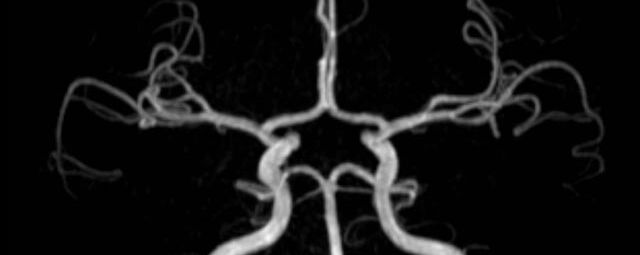

• intrakranielle Gefäße (Abklärung Verschluss, Stenose, Aneurysma)

MR-Angiografie (MRA)

• MR-Angiografie ohne Kontrastmittel

• Time of Flight (TOF)-Angiographie

Je nach Fragestellung und Körperregion Gefäßdarstellung ohne Kontrastmittel bei Kontrastmittelunverträglichkeit oder terminaler Niereninsuffizienz möglich.

• MR-Angiographie mit Kontrastmittel

• Erfassung arterieller und venöser Gefäße/Bypässe aller Körperregionen mit 3D-Rekonstruktion